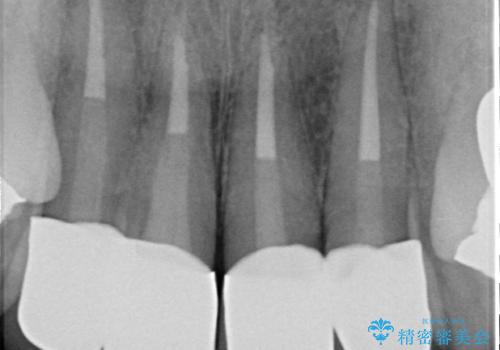

- 20年前に治療した前歯の劣化・審美障害の改善を求めて来院されました。

クラウンを除去し審美的なジルコニアクラウンによる補綴の再作製計画を立案します。

- 52万円(仮歯×4・ファイバーコア×4・ジルコニアクラウン×4)費用は治療当時の料金となります

クラウンと支台の適合が悪いと内部に汚れがたまり虫歯の再発・審美性の障害・口臭の発生リスク方あまります。